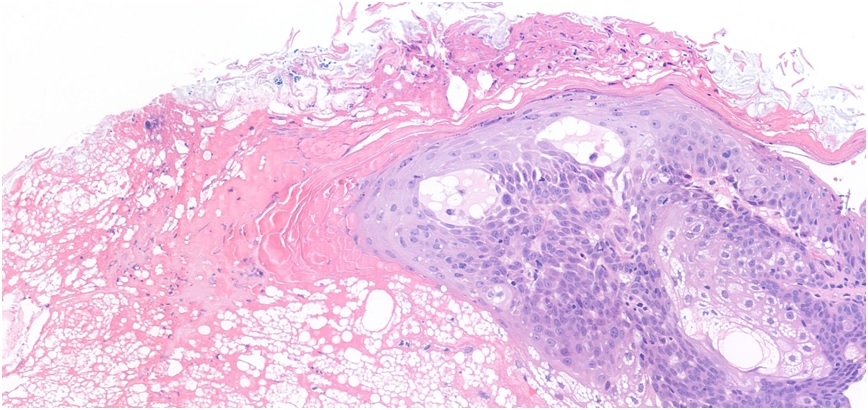

R temple ?C+C. 3 month history, 4 mm papule ?SCC ?BCC

A challenge to me. Looks like a sebaceous, but not enough. Looks like a sebaceous adenoma, but not enough. So it could really be a sebaceous carcinoma, couldn’t it?

I am leaning vs sebaceous adenoma or something benign adnexal (hidradenoma with extensive sebaceous metaplasia). I thought of sebaceous carcinoma but to my experience they are more mitotically active and have areas of necrosis